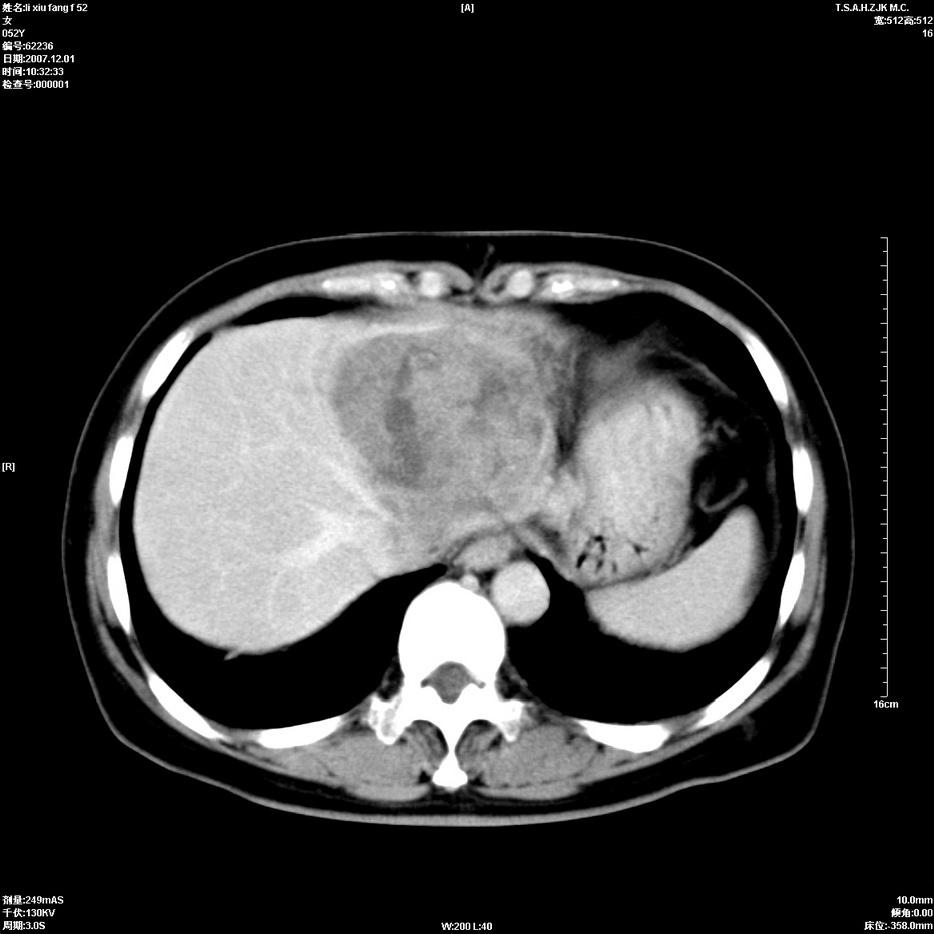

标题: CT12858:女,52岁,胎甲球蛋白861肝左叶占位,肝癌。下腔静 [打印本页]

标题: CT12858:女,52岁,胎甲球蛋白861肝左叶占位,肝癌。下腔静

肝左叶巨大低密度灶肿块,增强符合快进快出表现,有动静脉交通支;静脉期,下腔静脉内有充盈缺损,afp明显升高,支持肝癌并下腔静脉癌栓形成。

支持楼主   门静脉主干及左支癌栓形成

以下是引用拾荒者在2008-4-15 22:57:00的发言:[br]肝左叶巨大低密度灶肿块,增强符合快进快出表现,有动静脉交通支;静脉期,下腔静脉内有充盈缺损,afp明显升高,支持肝癌并下腔静脉癌栓形成。